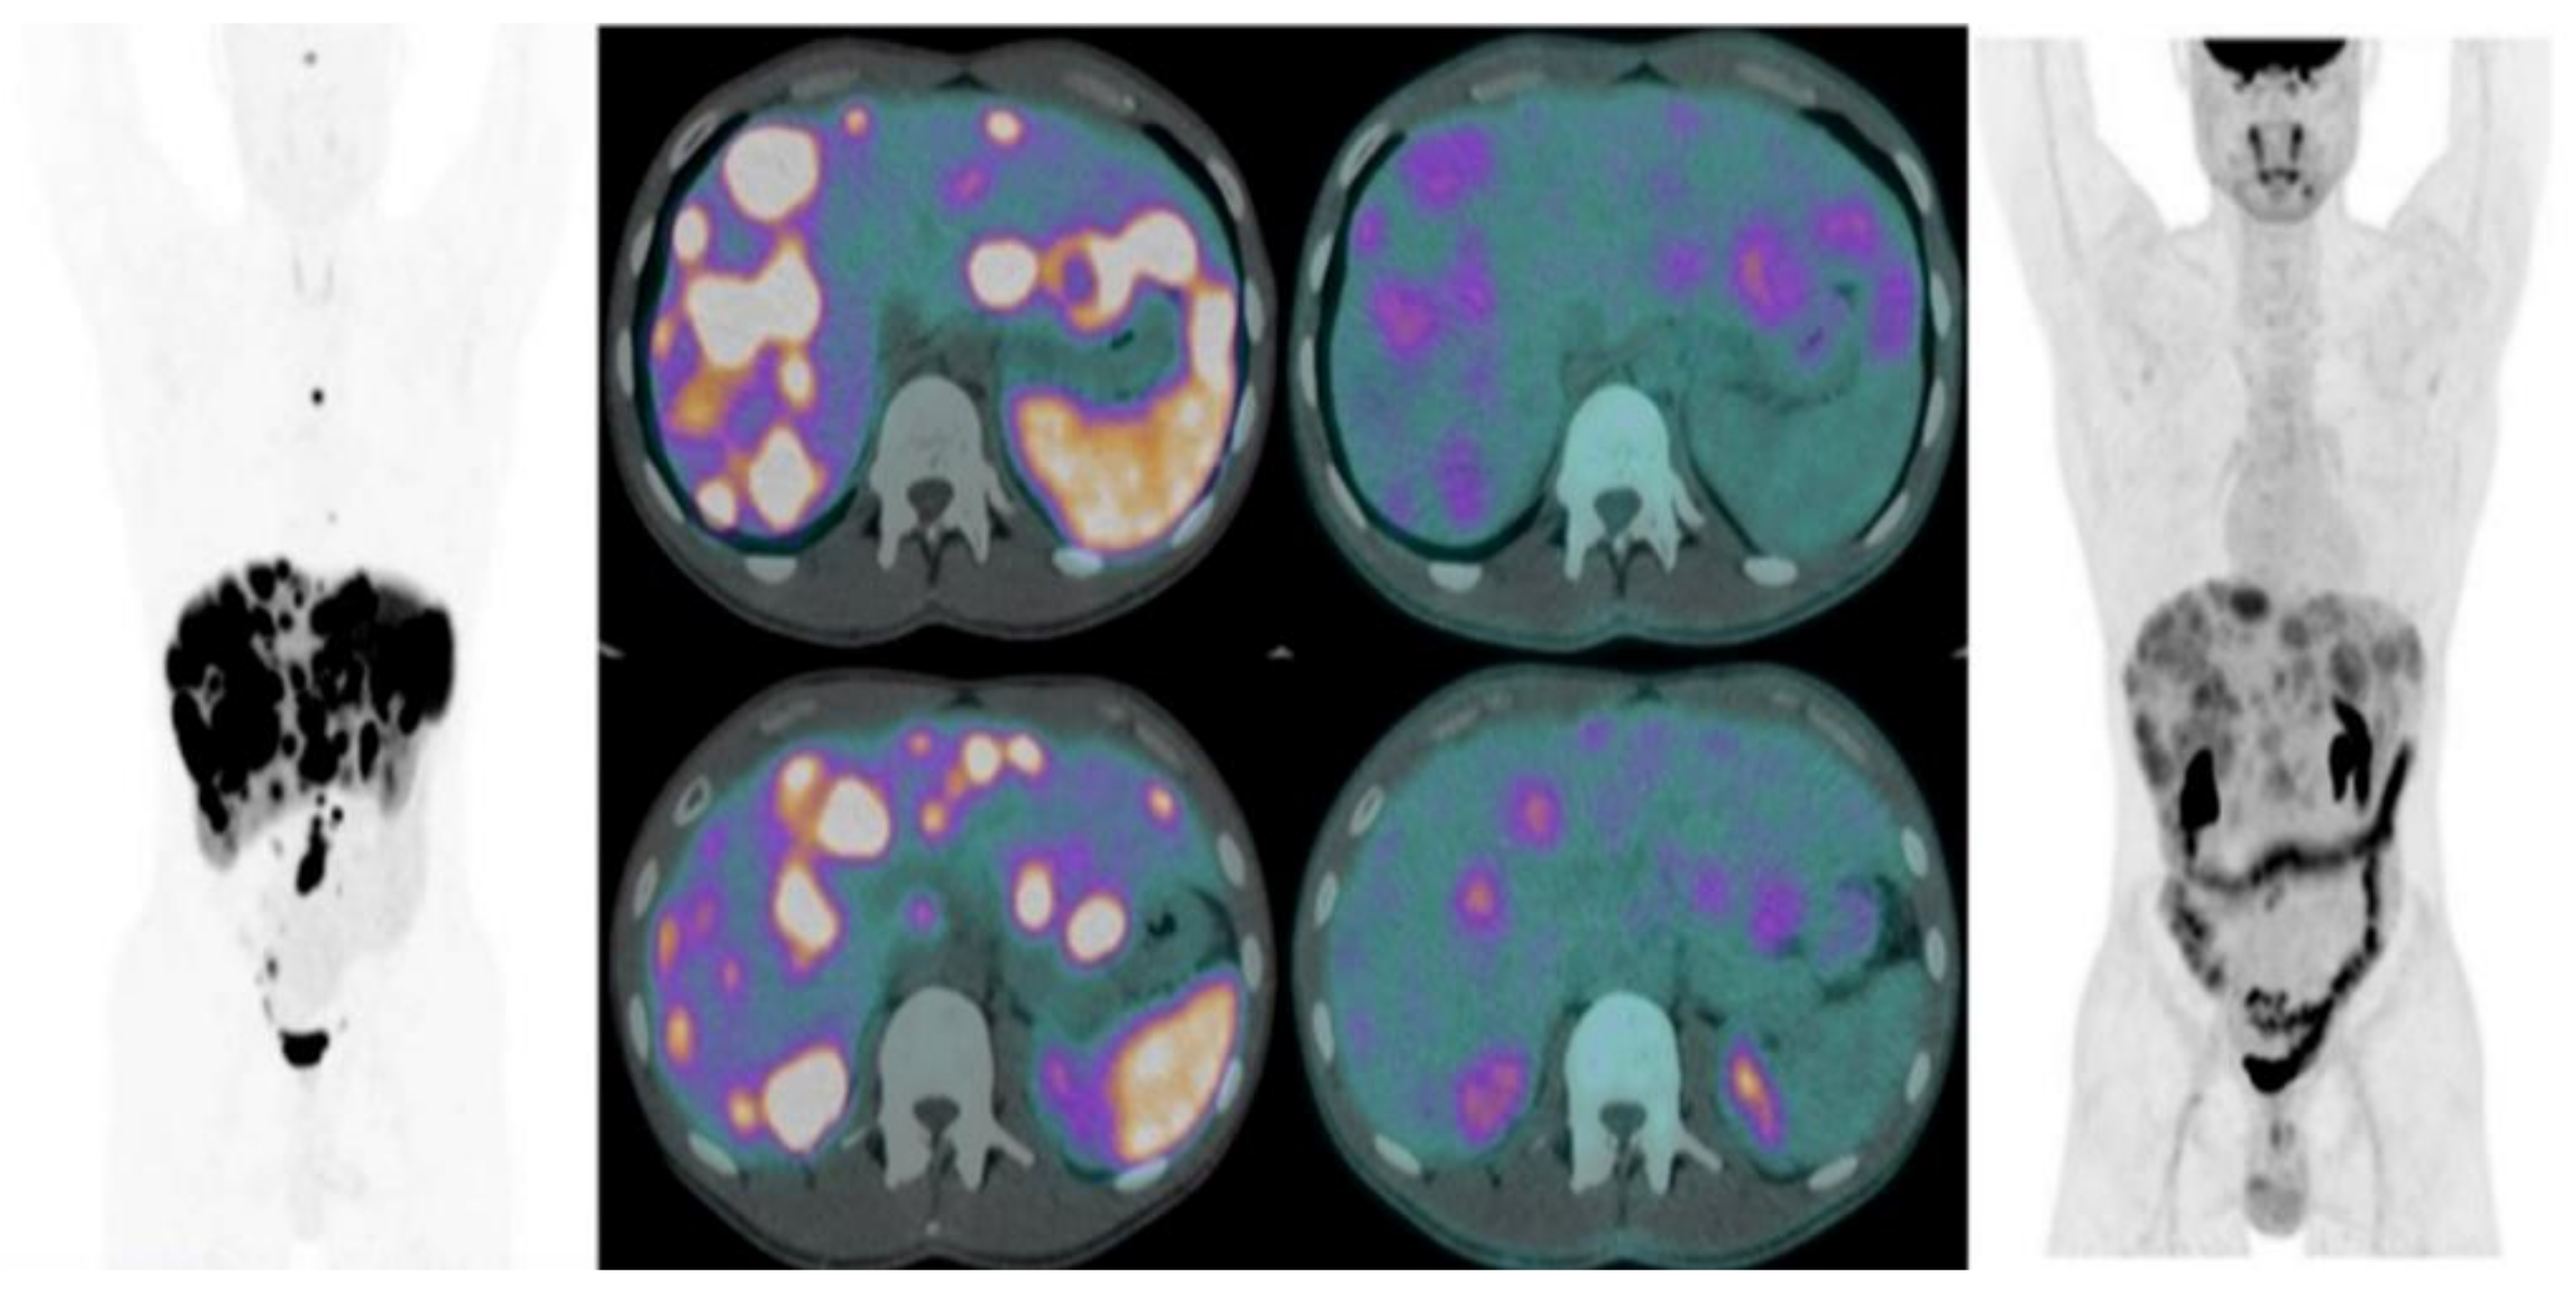

In the last few years, several papers have investigated the combined use of 18F-FDG and 68Ga-SSA PET/CT in the management of NENs, generally in intermediate- or high-grade panNETs, to obtain useful information on tumor heterogeneity, the characterization of SSTR expression, and tumor grade (Figure 3).

Figure 3.

Combined imaging 68Ga-DOTA-SSAs-PET/CT and 18FDG-PET/CT in G2 small bowel NET showing heterogeneity of the tumor.

Using a combined approach, two different aspects of tumor biology may be explored: 68Ga-SSA PET/CT can provide information about the expression of SSTRs, thus evaluating the grade of tumor differentiation and guiding to targeted therapies. Conversely, 18F-FDG PET/CT can assess the prognosis and tumor aggressiveness, both in the staging and in restaging, thus providing useful information for risk stratification. Indeed, when increased tumor aggressiveness is suspected in patients with well-differentiated metastatic NETS, 18F-FDG PET/CT scans should be always performed.